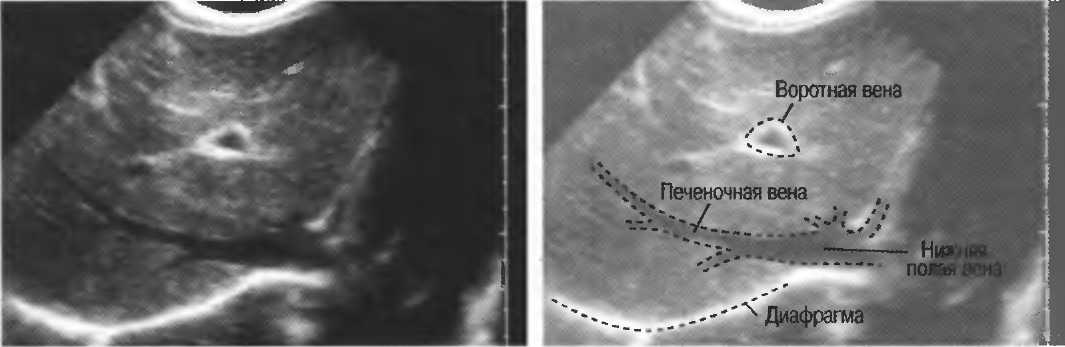

- Печеночные вены диаметром всего 3 мм должны визуализироваться при сканировании под углом 45° к поверхности нормальной печени (рис. 25).

Рис.25. Аппарат хорошего качества должен позволять визуализировать печеночные вены диаметром 3 мм. Этот тест может регулярно использоваться для контроля качества изображения.